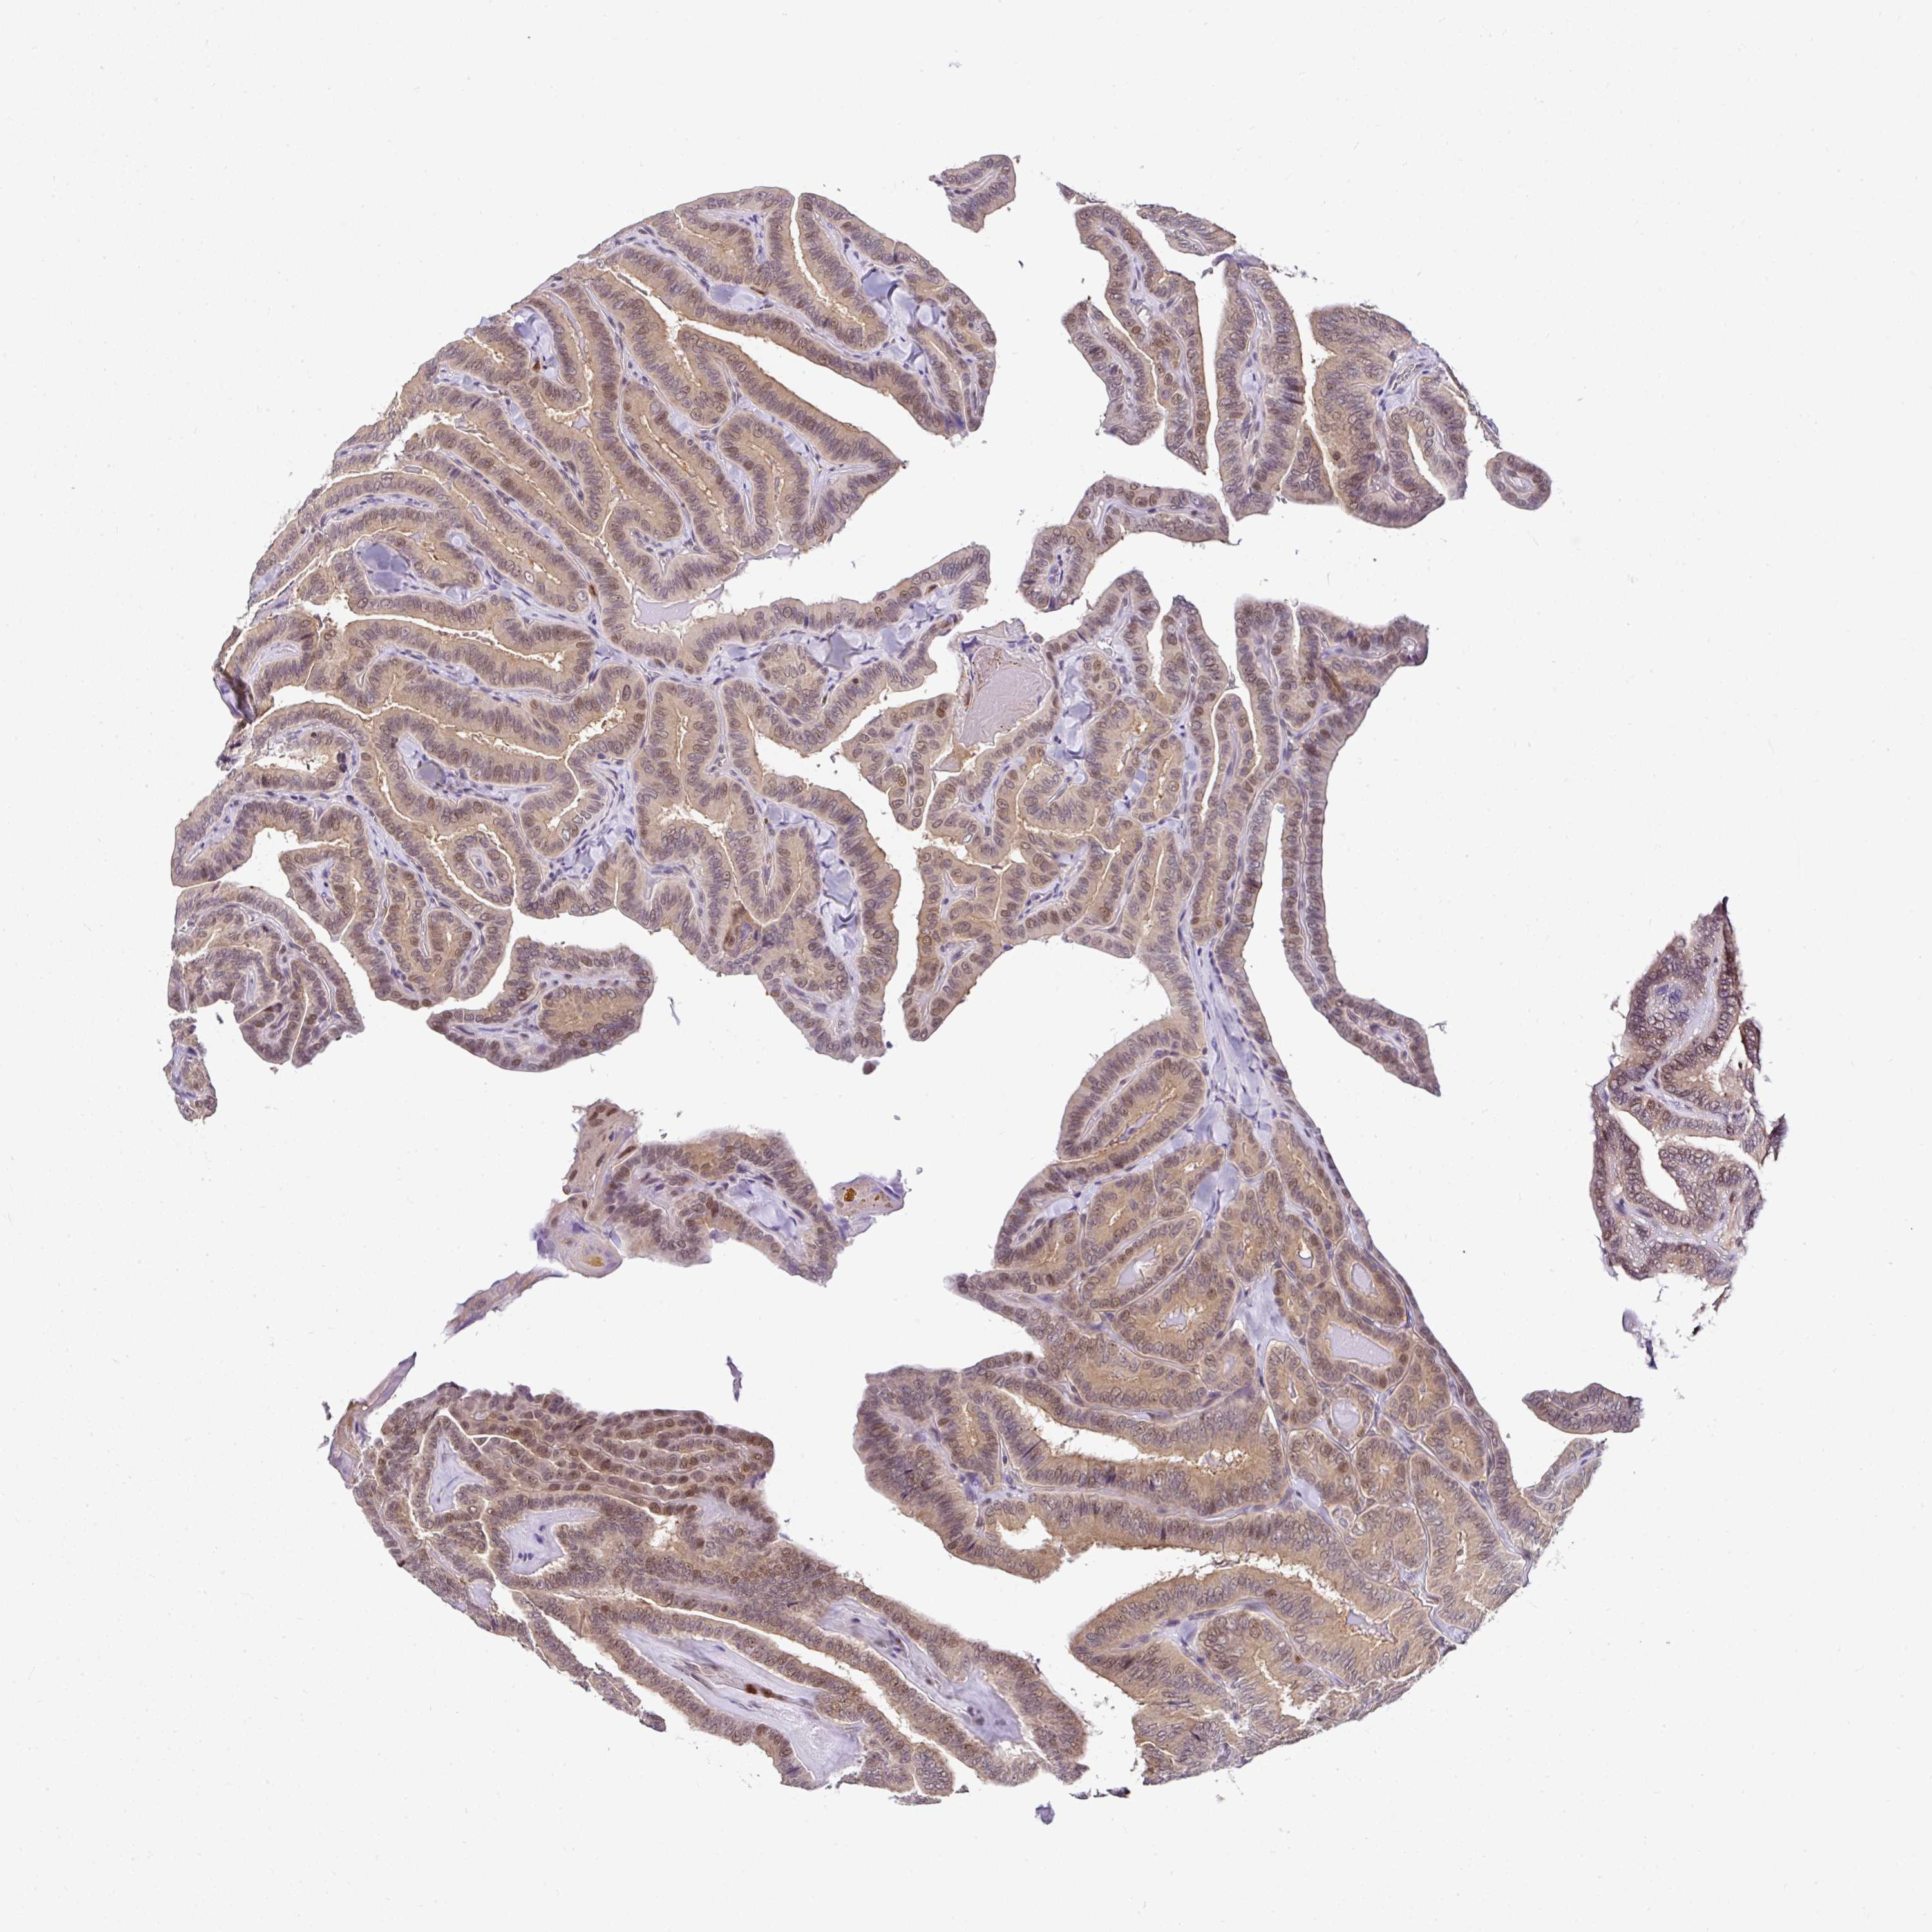

THYROID CANCER - Protein expressioni

A mouse-over function shows sample information and annotation data. Click on an image to view it in a full screen mode. Samples can be filtered based on level of antibody staining by selecting one or several of the following categories: high, medium, low and not detected. The assay and annotation is described here.

Note that samples used for immunohistochemistry by the Human Protein Atlas do not correspond to samples in the TCGA dataset.

Antibody stainingi

Antibody staining in the annotated cell types in the current human tissue is reported as not detected, low, medium, or high, based on conventional immunohistochemistry profiling in selected tissues. This score is based on the combination of the staining intensity and fraction of stained cells.

Each image is clickable and will lead to virtual microscopy that enables deeper exploration of all samples and also displays staining intensity scores, fraction scores and subcellular localization as well as patient and tissue information for each sample.

Antibody HPA054483

Antibody HPA064504

Staining

High

Medium

Low

Not detected

Intensity

Strong

Moderate

Weak

Negative

Quantity

>75%

75%-25%

<25%

None

Location

Nuclear

Cytoplasmic/membranous

Cytoplasmic/membranous,nuclear

Papillary adenocarcinoma, NOS

Follicular adenoma carcinoma, NOS